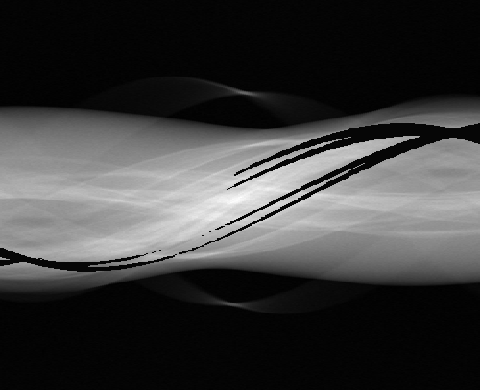

In practice, the complex wavelet transform is an effective tool for extracting singularities from a signal, as previously demonstrated for CT wavefront set extraction in [39]. In images and volumetric data, large-magnitude wavelet coefficients typically occur near jumps and edges. See Fig. 1 for an example of a sinogram containing two metal inserts, where the sum of the absolute values of the wavelet coefficients reveals the corresponding metal boundaries.

| 3D sinogram | ![]() |

![]() |

|---|---|---|---|---|

|